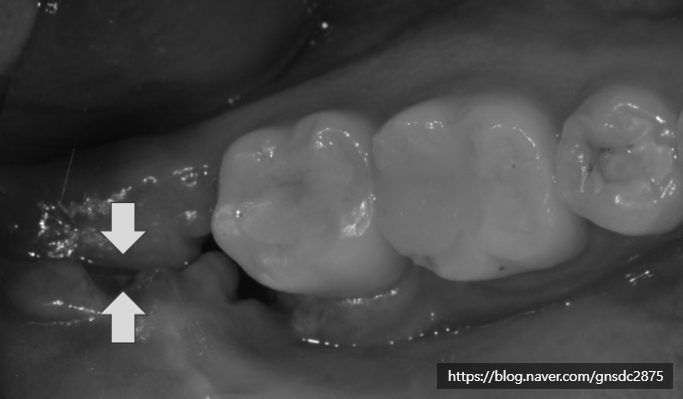

✅음식물 끼임

발치 후 구멍은 깊고 넓은 경우가 많아

음식물이 쉽게 끼일 수 있습니다.

음식물이 구멍에 남아 세균이 증식하면

염증이나 통증을 유발할 가능성이 있습니다.

발치 후 구멍 관리법

위와 같은 문제를 예방하기 위해

✅세척과 위생 관리 (양치법/가글)

잇솔질은 평소처럼 하시되

뽑은 곳은 조심해서 양치하며

발치부위에 음식물이 끼지 않도록

물로 자주 가볍게 헹궈주시는 게 좋습니다.

만약 음식물이 구멍에 끼어

물로도 빠지지 않는다면

치과에 방문하여 소독과 함께 빼내는 것이 좋습니다.